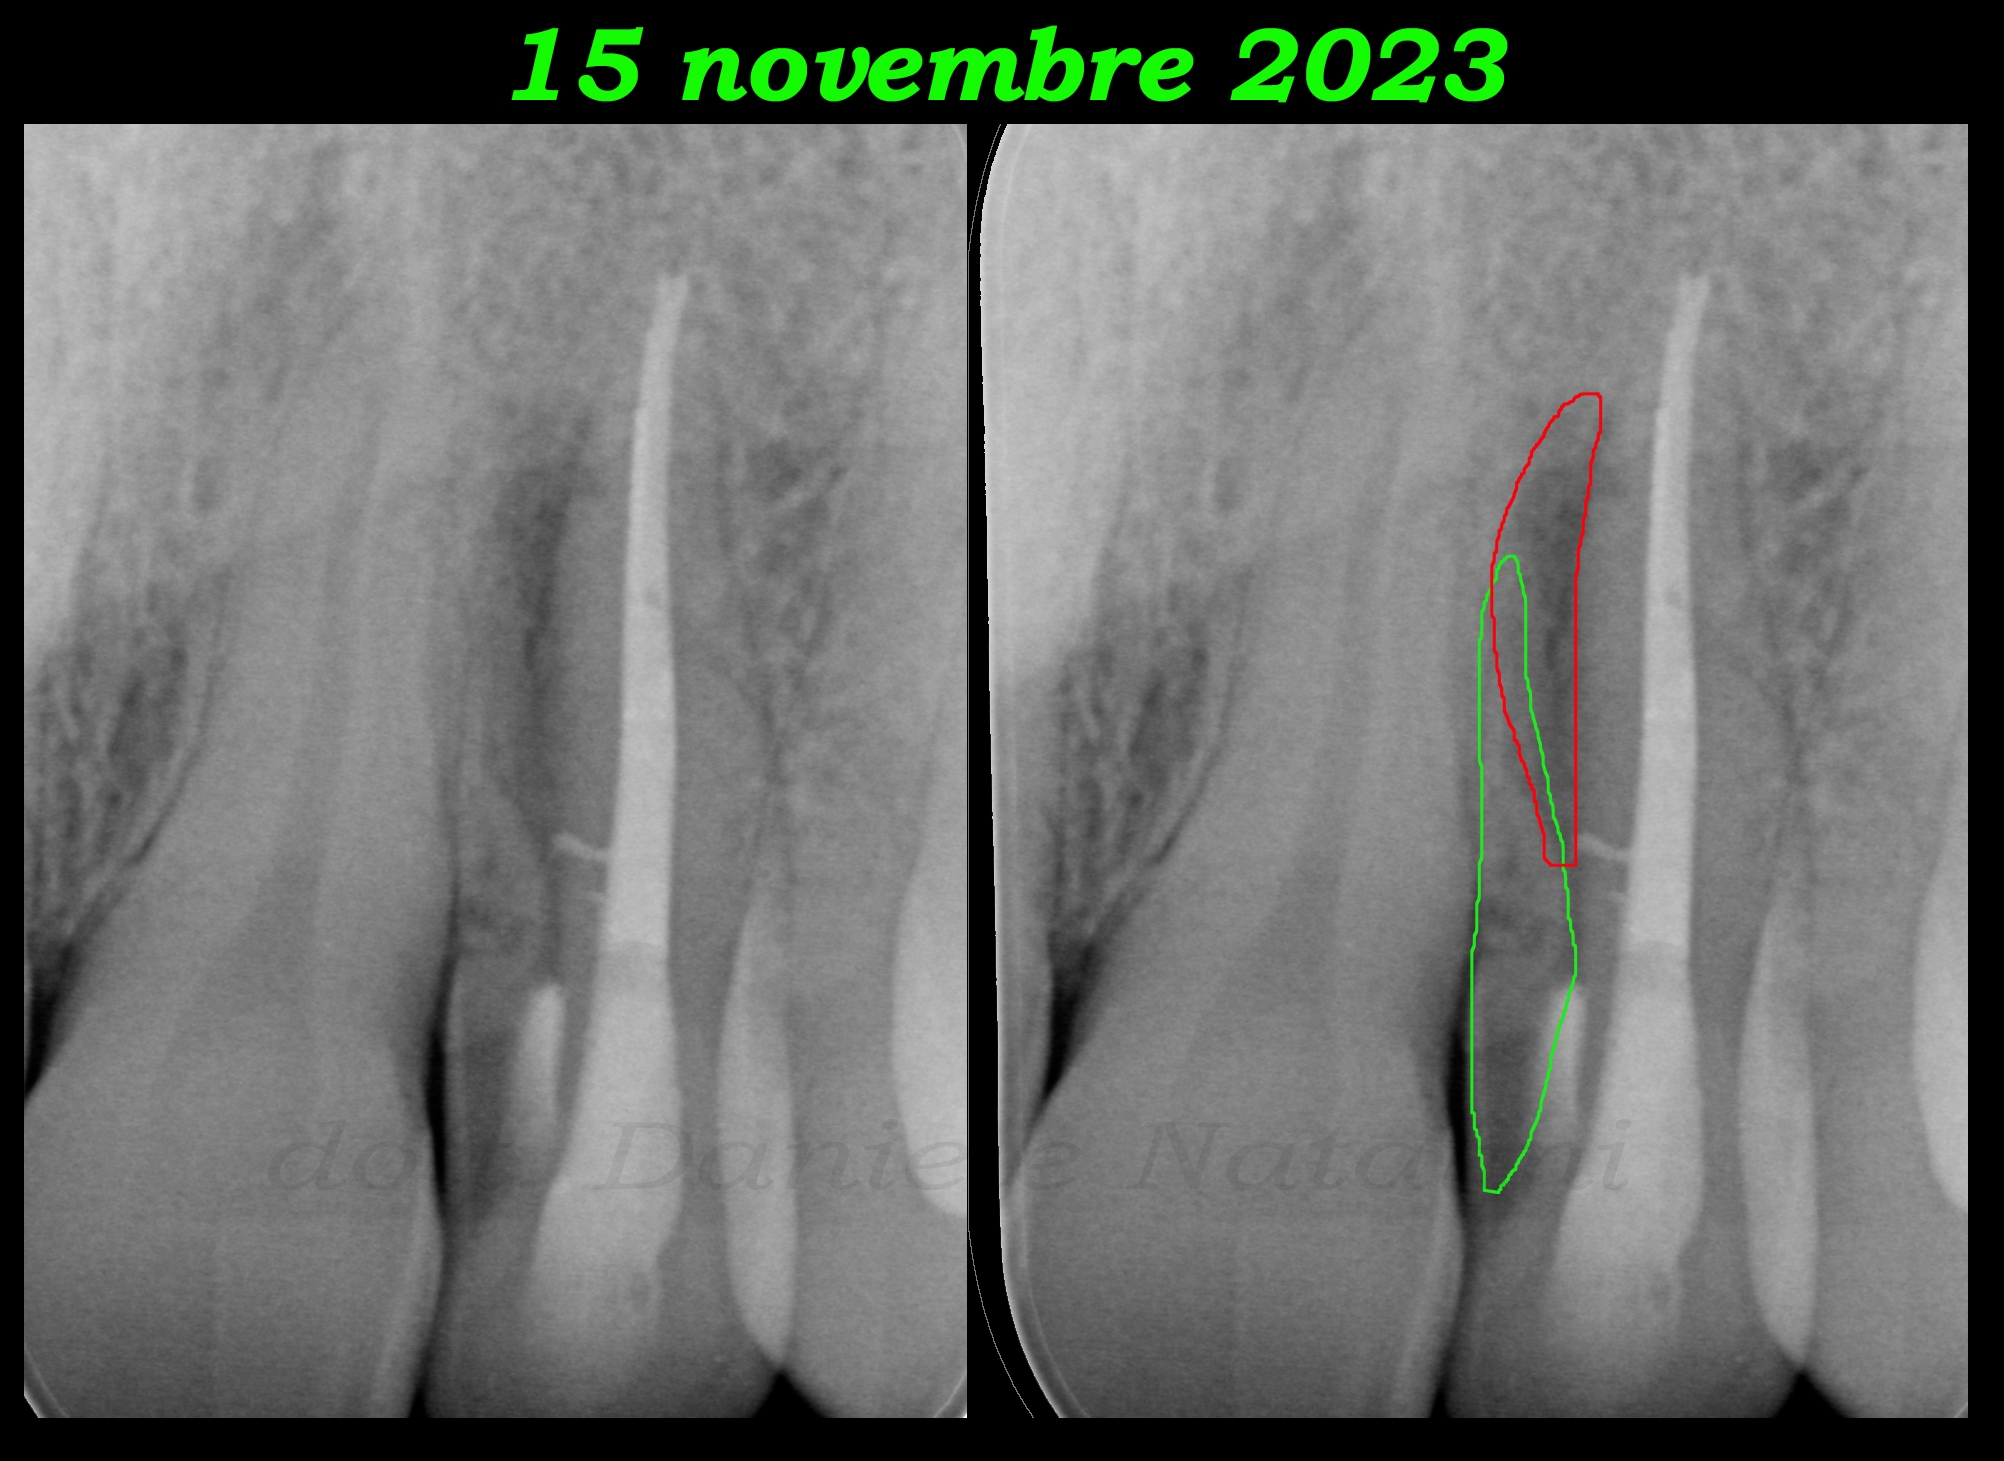

A novembre 2023, 16 mesi dopo, il paziente riferisce nuovamente sintomatologia e rigonfiamento a livello della mucosa. Non c’è più il sondaggio vestibolare, come evidenziato dalla foto a fianco, ma dalla nuova endorale l’immagine mesiale della radice accessoria appare più nitida grazie anche all’alone di radiotrasparenza determinato dalla nuova lesione.

Nov. 2023A novembre 2023, 16 mesi dopo, il paziente riferisce nuovamente sintomatologia e rigonfiamento a livello della mucosa. Non c’è più il sondaggio vestibolare, come evidenziato dalla foto a fianco, ma dalla nuova endorale l’immagine mesiale della radice accessoria appare più nitida grazie anche all’alone di radiotrasparenza determinato dalla nuova lesione.